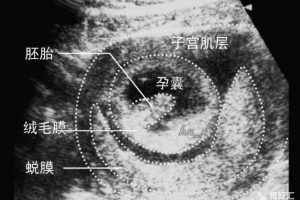

生化妊娠是什么,生化妊娠会排出孕囊吗?生化后多久可以怀孕?

什么是“生化妊娠”  很多人或许没有听说过“生化妊娠”,但是它在实际的生活中却具有较高的发生率和所占比例。据统计,大约有50-60%的初次怀孕最终都以流产告终,其中绝大部分都可以归结为“生化妊娠”。此外,约有25%的女性在怀孕时并不知情,反而把自己所遇到的月经推迟视为日常的例行公事。  实际上,…